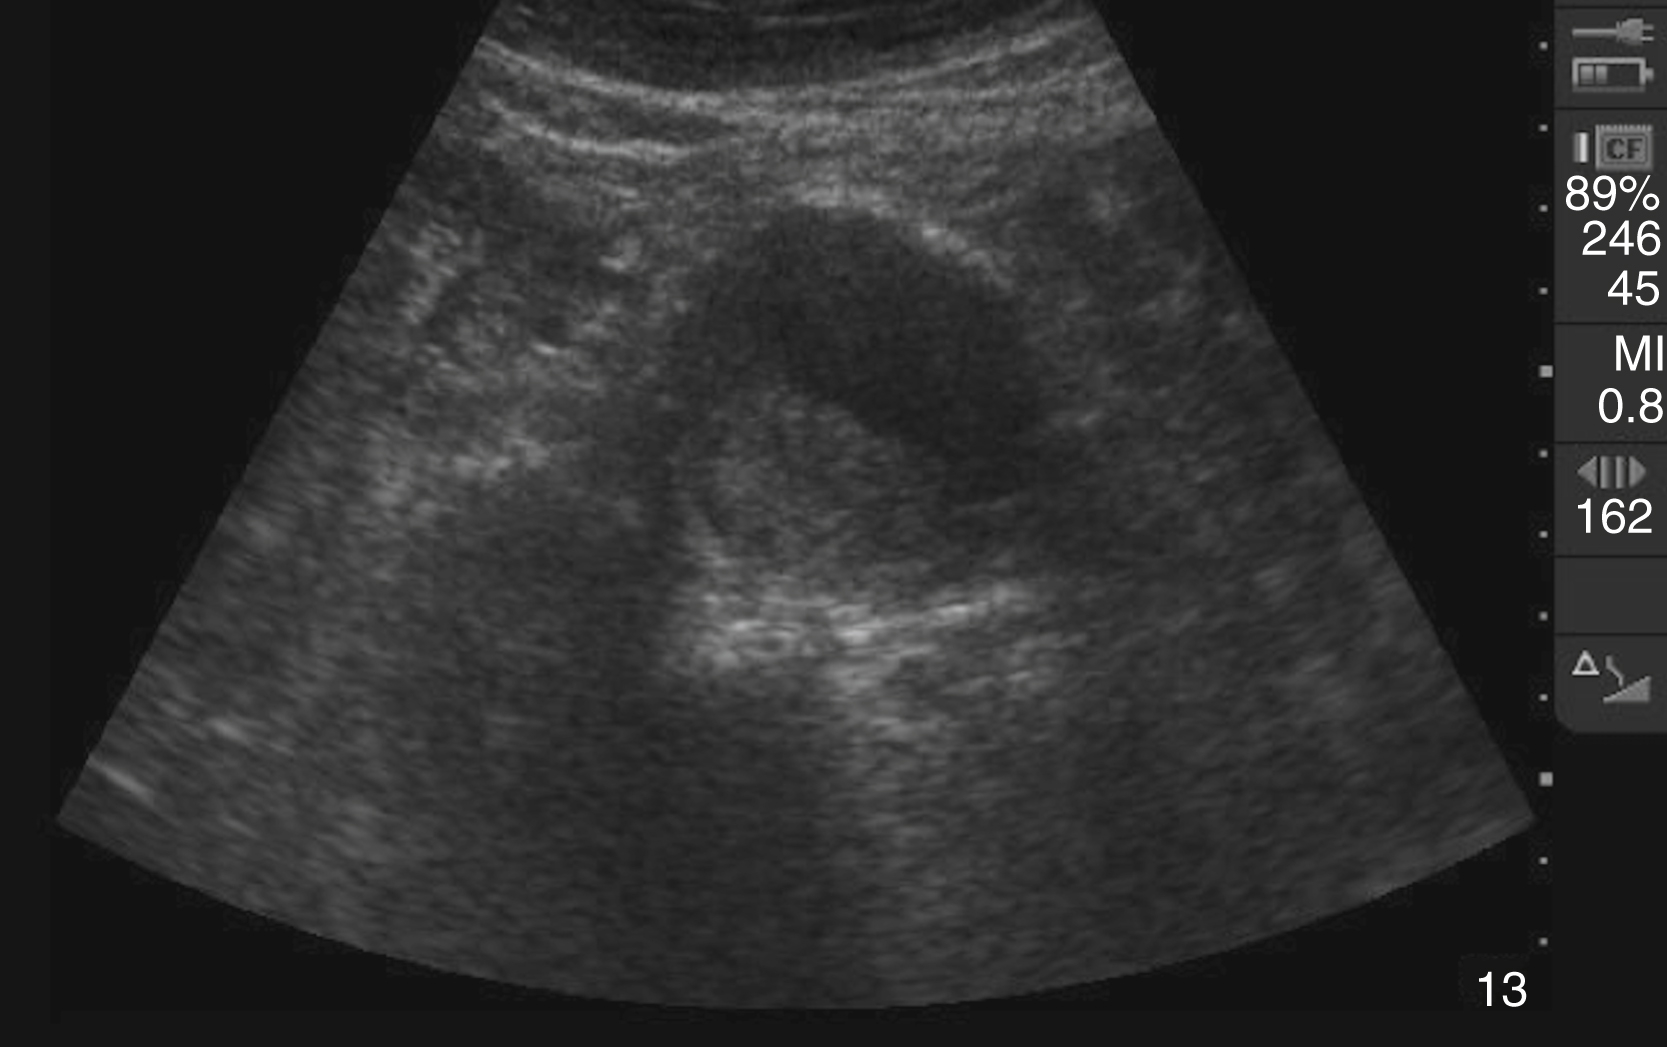

The diagnosis of cholelithiasis is made by identification of echogenic foci within the gallbladder lumen with associated shadowing. Other image patterns include stones with indistinct shadow, sludge, and the wall-echo-shadow (WES) sign seen in a gallbladder full of gallstones ( Video e3.5 ). Although many sonographic findings can be seen with AC, including gallstones, dilated gallbladder, increased gallbladder wall thickness (>3 mm), sonographic Murphy sign, pericholecystic fluid, and CBD dilatation, gallstones are present in 95% to 99% of AC cases ( Fig. e3.4 ). A nonmobile stone in the gallbladder neck, confirmed in the left lateral decubitus position, is highly suggestive of eventual cholecystitis. A CBD larger than 6 mm in people younger than 60 years and larger than 10 mm in older patients may indicate choledocholithiasis.

Sagittal gallbladder with signs of acute cholecystitis including stones with posterior shadowing, thickening of the wall anteriorly, and pericholecystic fluid seen within the wall of the gallbladder.